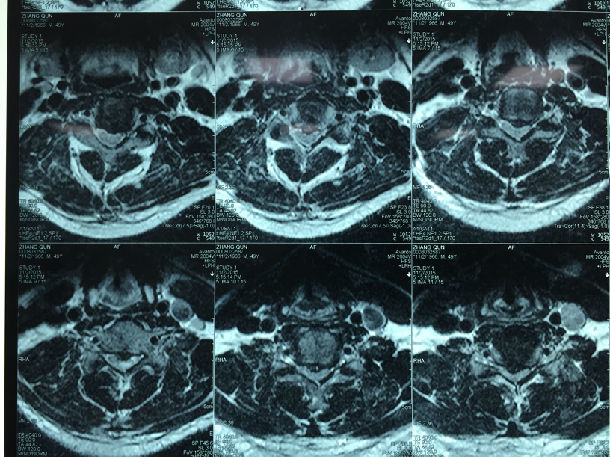

手术前-多节段颈椎间盘突出/黄韧带肥厚/颈椎管狭窄-脊髓损伤

显微镜下经颈后路行单开门椎管扩大成形术-颈椎管明显增宽/脊髓受压解除/患者逐渐康复